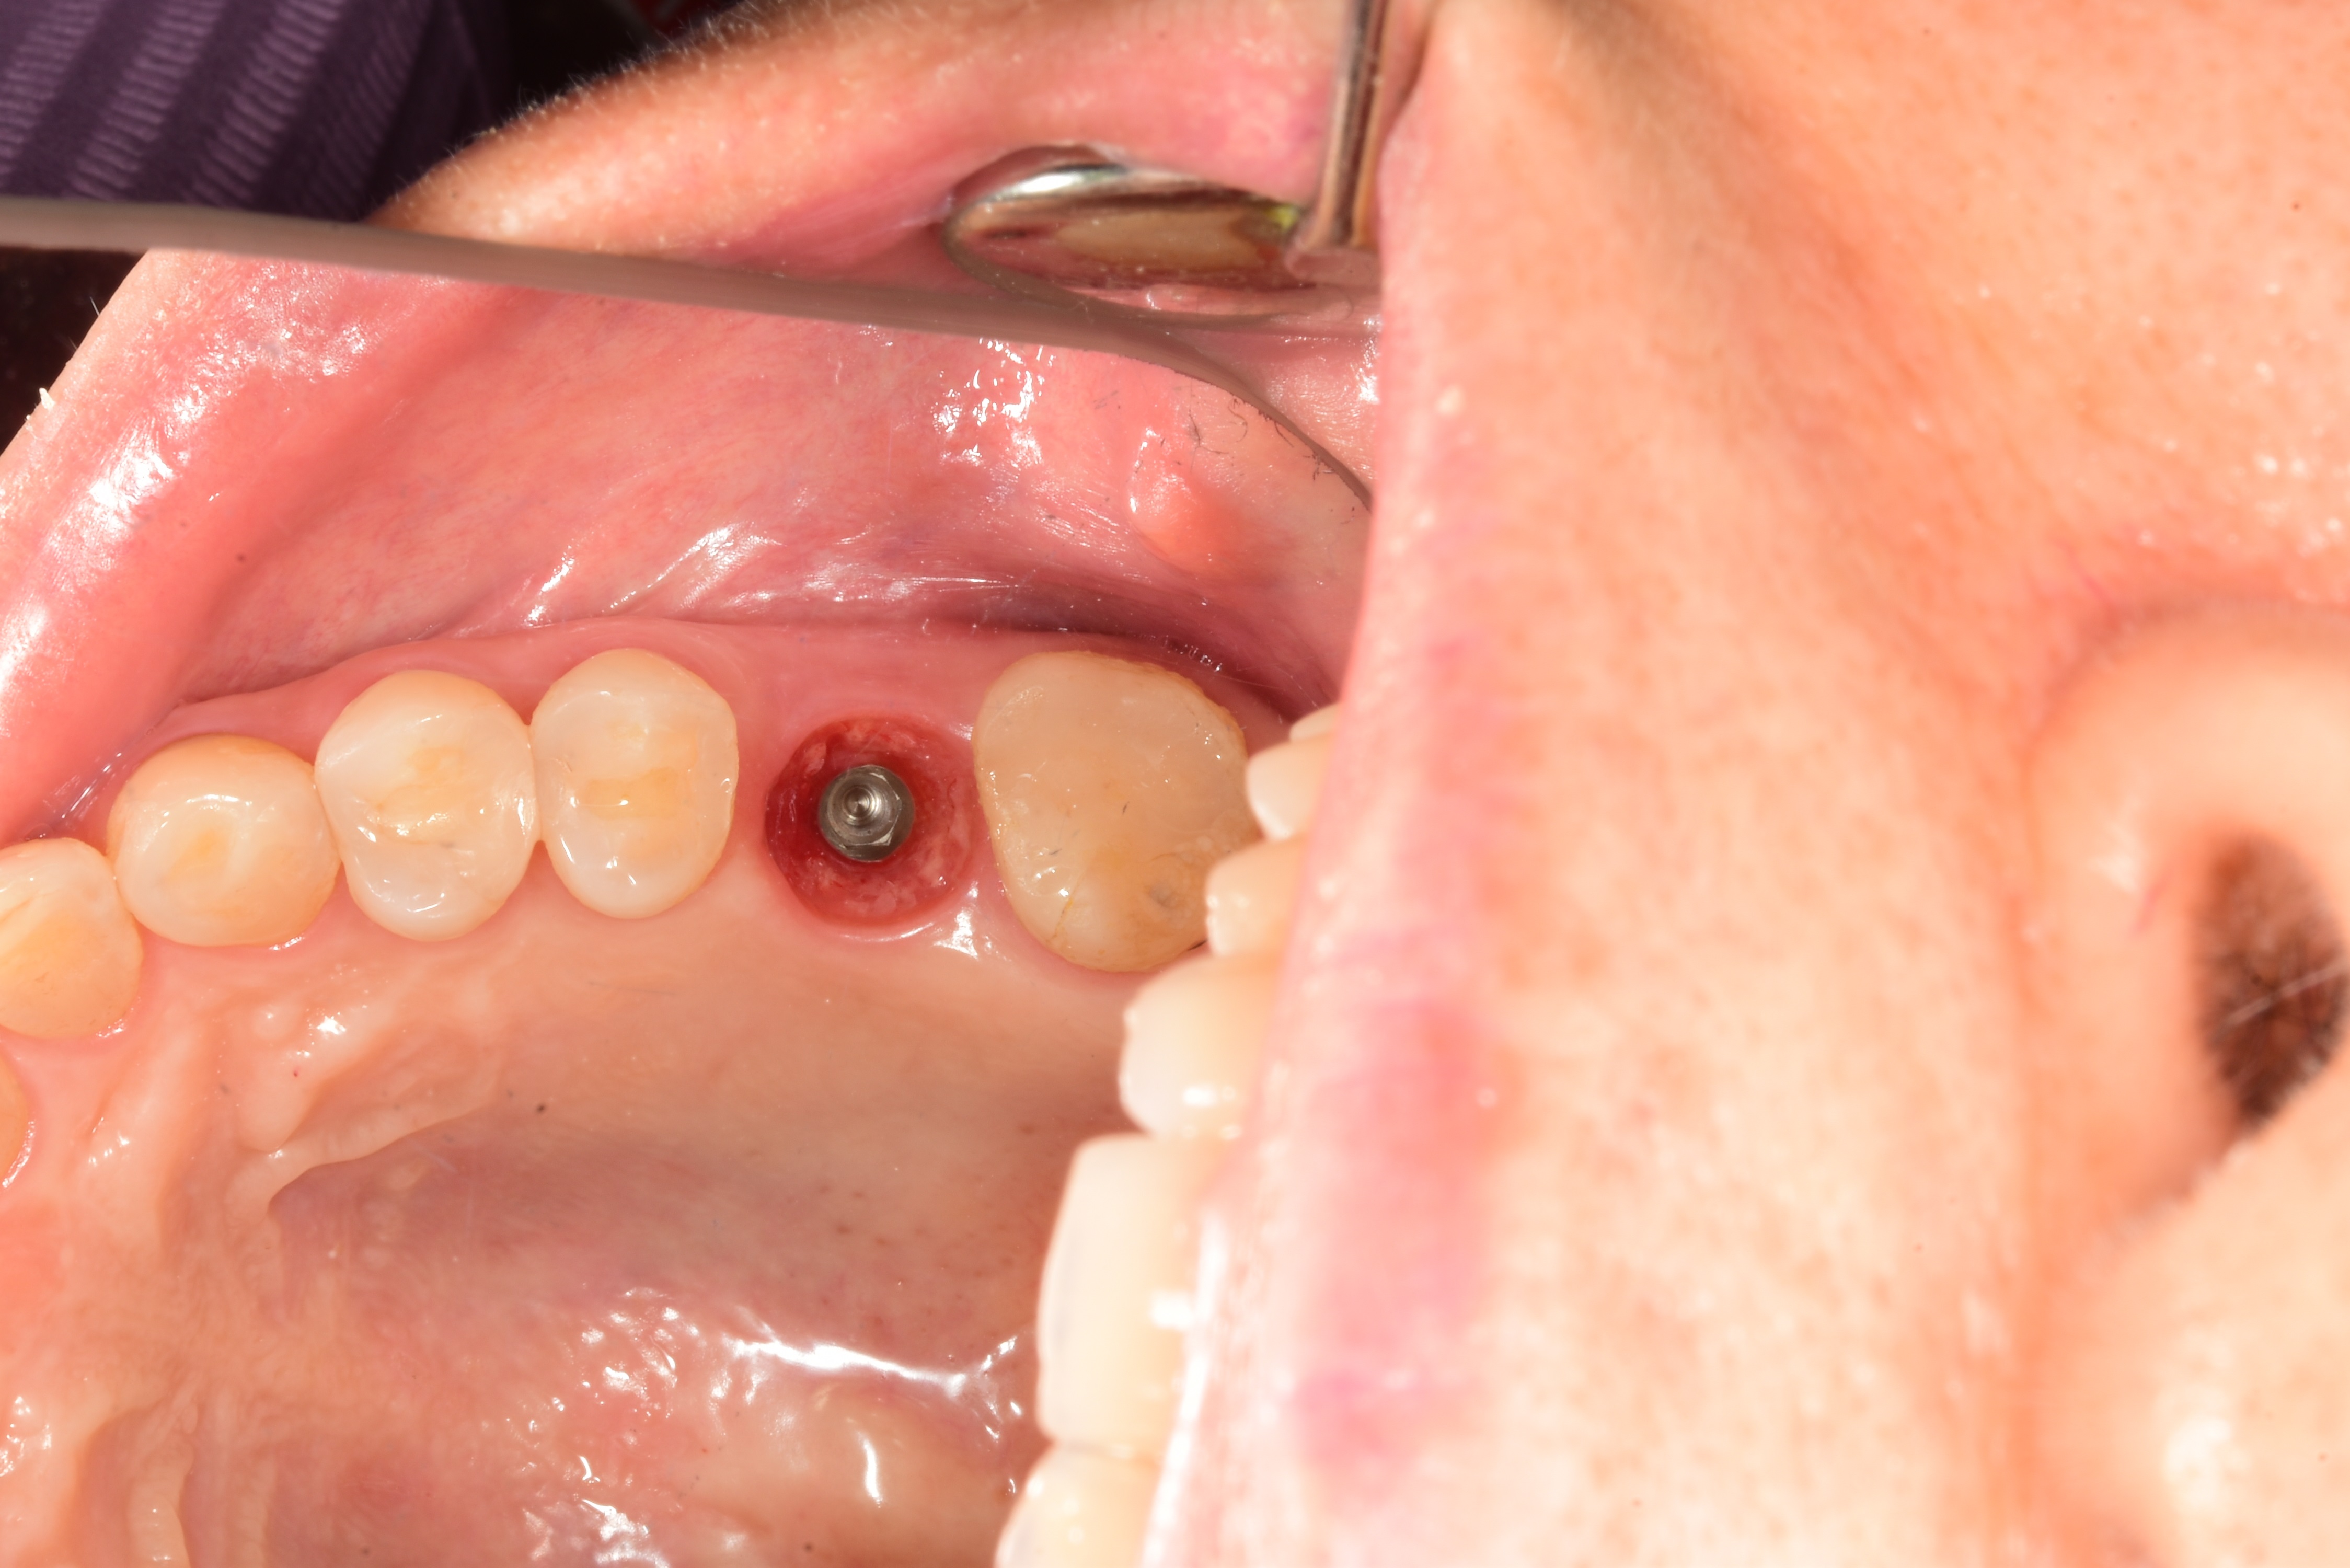

案例四

使用數年的假牙,牙根萎縮,建議拔除及植牙

醫生透過電腦斷層評估骨頭狀況決定植入的植體所放的寬度與深度

植入植體,並鎖上癒合螺帽

2-3個月癒合,7-10天完成假牙 ,試戴、調整咬合高度並鎖上,封填,完成